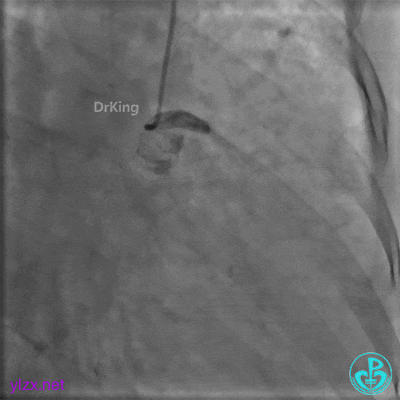

经微导管造影。

远段造影剂外渗在增加,怎么办?

微导管送入PL分支远段,取明胶海绵颗粒栓塞剂1ml通过微导管向远端血管推注栓塞远端血管。